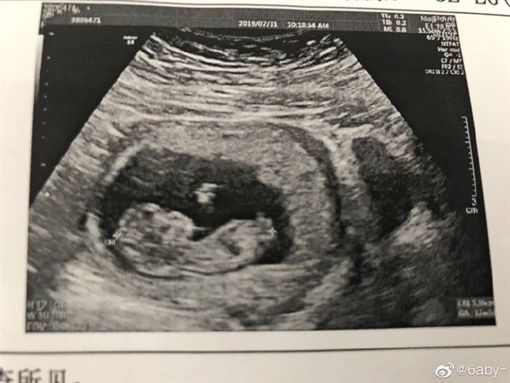

抖音爆紅的情侶羊羊羊和女友小可愛在今年初終於攜手步入禮堂,求婚影片後更是感動了無數的網友,羊羊羊更實現對女友的承諾,將婚禮現場佈置成「仙境」,還哽咽地向女友告白:「我等這一刻等了好久,我的願望就是一生一世跟妳在一起」如同電影般的場景,羨煞不少人。事隔5個月,近日小可愛在微博公開一張超音波照,文章一曝光,粉絲紛紛湧入祝福。

照片中,小可愛雙手拿著印有超音波照片的紙張,小倆口都露出幸福又滿足的笑容,向全天下昭告好消息之餘,也對肚子裡的小孩說道:「寶貝,爸爸媽媽歡迎你來到這個世界,我們一定會把最好的愛都給你。謝謝你讓我們有了新的身份,希望你健康成長、平安快樂,等待你的到來。」老公羊羊羊同時也在社群平台感性地說:「期待我們全新的家庭模式1+1=3。」